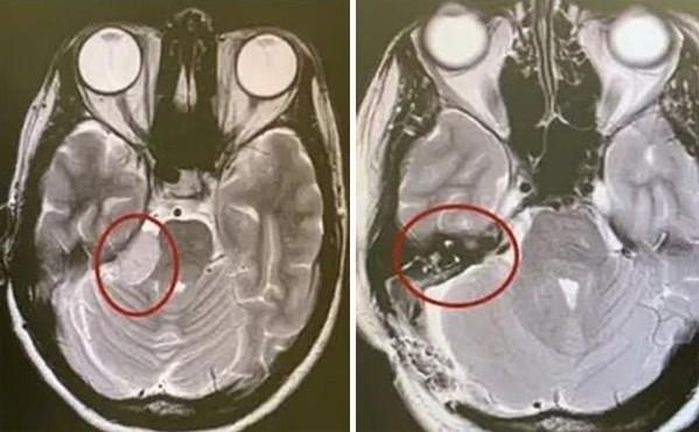

Bệnh nhân có khối u não kích thước lớn, nhập viện trong tình trạng nguy kịch, các bác sĩ đã tiến hành phẫu thuật cấp cứu cứu sống bệnh nhân.

Bệnh viện Nhi Thanh Hóa phẫu thuật thành công cho bệnh nhi 10 tuổi, bị u tiểu não kích thước lớn.

Các bác sĩ khoa Phẫu thuật Thần kinh - Lồng ngực, Bệnh viện Đa khoa tỉnh Thanh Hóa, vừa cắt bỏ thành công khối u tiểu não bên trái phức tạp bằng kính vi phẫu.